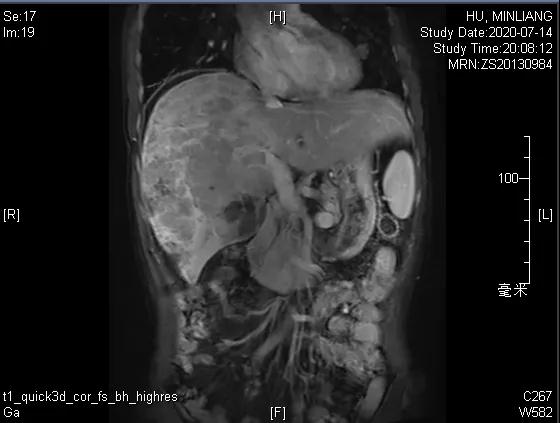

术前影像学检查:

肝脏弹性超声:12kPa。腹部MRI平扫+增强:肝巨块结节性HCC(最大径18.4cm)伴肝内多发转移(最大径3.5cm),肝右静脉广泛癌栓形成;肝硬化伴门脉高压、脾大、少量腹水;肝囊肿;双肺多发转移。胸部CT平扫:两肺多发转移,两肺气肿伴肺大泡,两肺散在慢性炎症,右侧少量胸水。

Δ肺CT:双肺多发转移